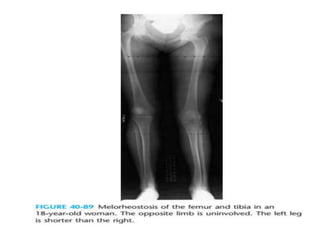

typically affects one limb or one side

Anteroposterior radiographs

demonstrate the classic dripping

candle wax appearance of cortical

and medullary hyperostosis involving

the lateral aspect of the femur

typically affects onelimb or one side

Anteroposterior radiographs demonstrate theclassic dripping candle wax appearance of cortical and medullary hyperostosis involving the lateral aspect of the femur